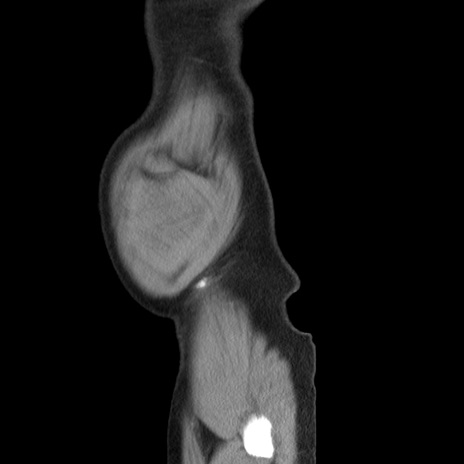

症例20(矢状断像)

【症例】 60歳代男性

【主訴】 腹部膨満、嘔吐

【現病歴】5日前頃より倦怠感を認め食事量減少し4日前の朝嘔吐、食事摂取困難となった。 3日前近医受診し点滴施行され整腸剤などを処方された。 当日他院を受診し、腹部膨満著明、炎症反応の上昇(CRP10.8、WBC11200)あり、紹介受診となる。

【身体所見】 意識JCS1 受け答えがはっきりしないBP 111/57mHg、 P 67bpm、、BT35.2°C、SpO2 97%(RA)、 腹部:膨隆、打診で鼓音あり、全体的に圧痛有り、腸蠕動音(-)、反跳痛ははっきりせず。

【データ】WBC 11400、CRP 14.20